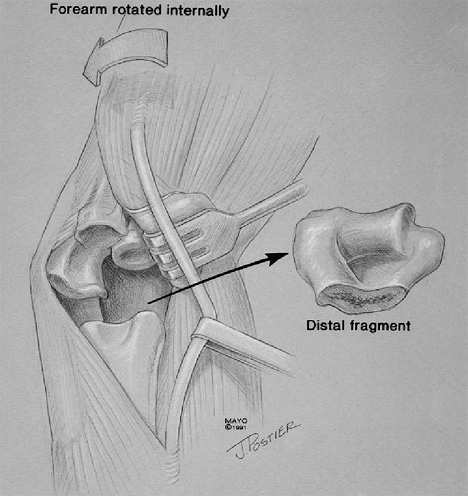

the patient with a grossly unstable elbow due to a distal humeral

nonunion or prior resection.

humerus allows ready access to the humeral canal by translating the

distal segment to the lateral margin of the triceps muscle. For acute

fracture or for nonunion, we first excise all fragments while leaving

the triceps left attached to the olecranon (Fig. 18-40) (2,7).

Figure 18-40. The distal humeral nonunion or acute fracture is excised, leaving the triceps attached.